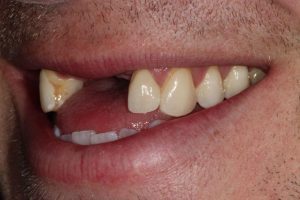

Broken Upper Front Tooth

The upper right central incisor tooth broke and was irreparable. Following removal of this tooth, and implant was placed on the same day as well as a temporary crown. This gave the patient a replacement tooth immediately and after 3 months of healing, a more definitive crown was made to match closely the adjacent tooth.